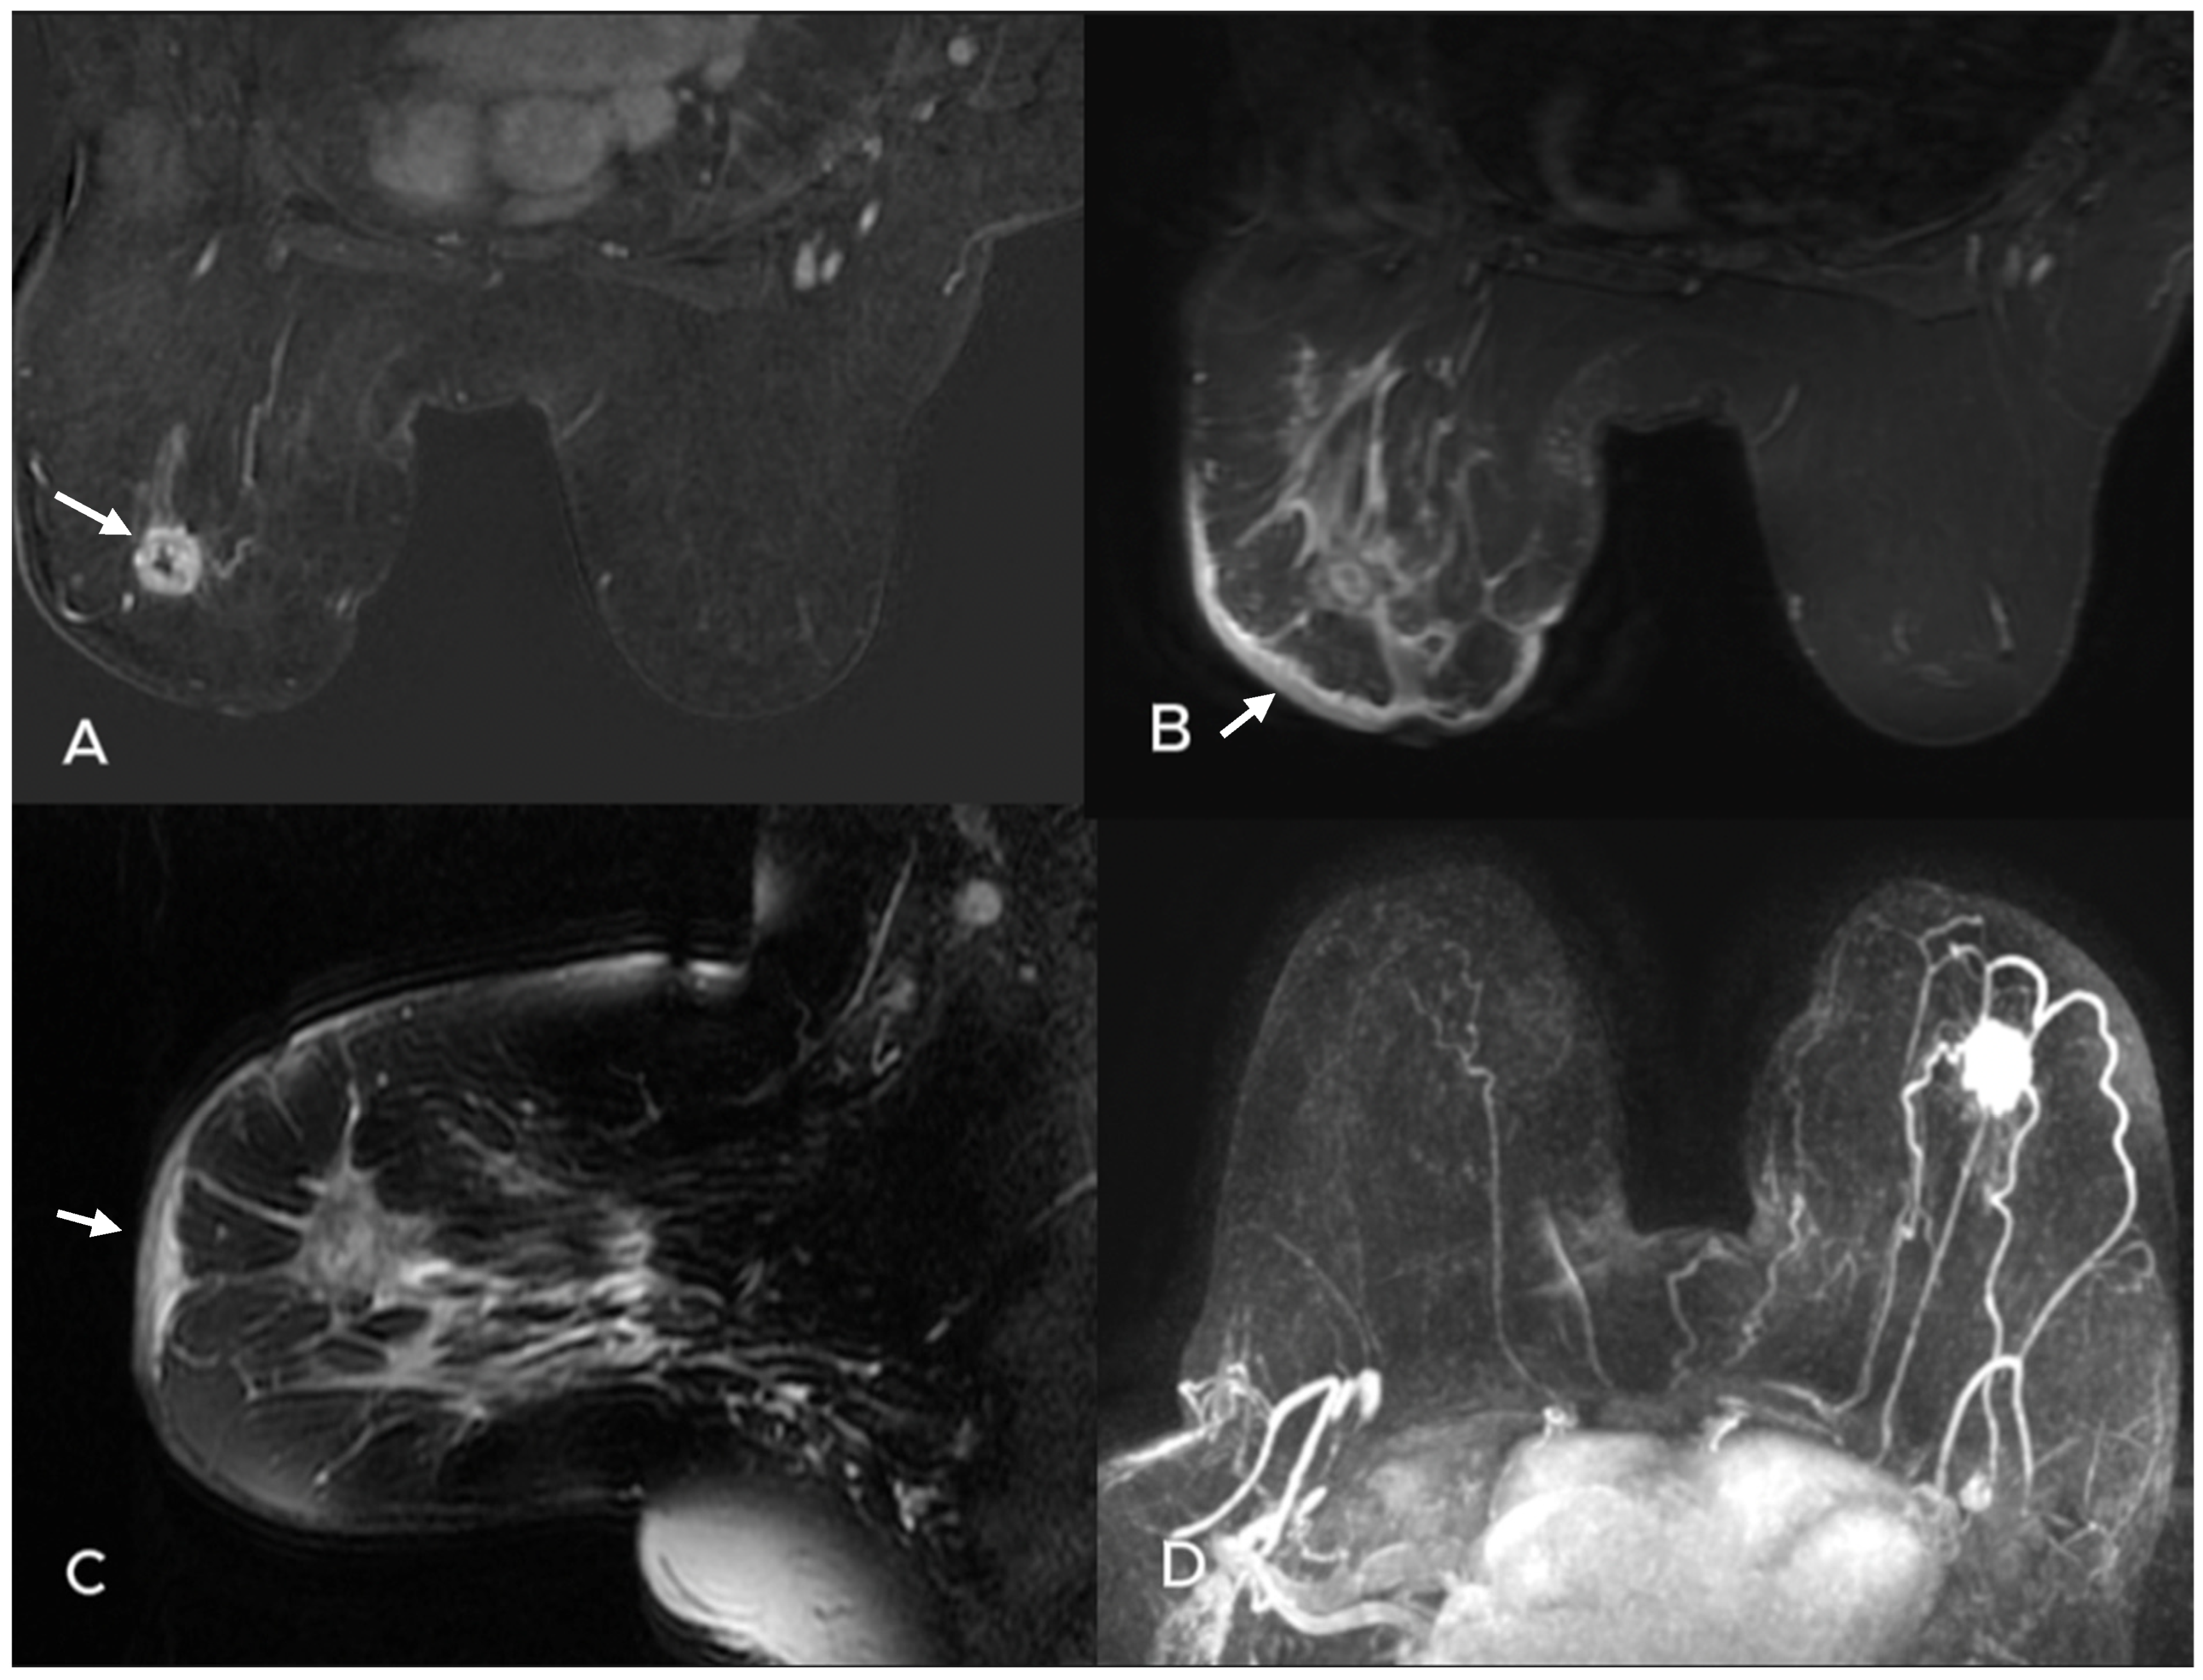

- Uematsu, T. Focal breast edema associated with malignancy on T2-weighted images of breast MRI: Peritumoral edema, prepectoral edema, and subcutaneous edema. Breast Cancer 2015, 22, 66–70. [Google Scholar] [CrossRef]

- Akdoğan Gemici, A.; Tokgoz Ozal, S.; Hocaoğlu, E.; Arslan, G.; Sen, E.; Altınay, S.; İnci, E. Relation of peritumoral, prepectoral and diffuse edema with histopathologic findings of breast cancer in preoperative 3T magnetic resonance imaging. J. Surg. Med. 2019, 3, 49–53. [Google Scholar]